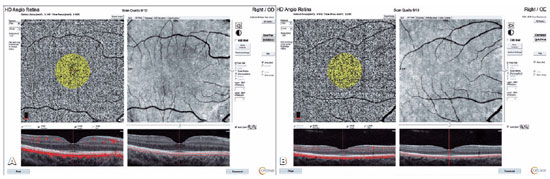

OCTA

All images were captured with the AngioVue Imaging System (RTVue XR Avanti; Optovue, Inc., Fremont, CA, USA) by the same qualified observer. The AngioVue Imaging System is a spectral-domain OCT device that supports concurrent three-dimensional anatomical imaging of the retina and produces en face projections of the blood flow within a split-spectrum amplitude-decorrelation angiography algorithm. The AngioAnalytics software (Optovue, Inc.) provides the area of the foveal avascular zone (FAZ) and capillary vessel density (VD) from the selected areas of the retina. Quantitative analysis of 6 × 6 mm OCT angiograms was taken for the automated detection of flow including the FAZ (mm2), capillary VD (%), and choriocapillaris flow area (mm2) analysis. The device automatically embedded three fovea-centered concentric circles on the macula by a density estimation device in both superficial capillary plexus (SCP) and deep capillary plexus (DCP) (Figure 1A). The VD was automatically calculated by the OCTA scanner. The SCP was located between 3 µm below the inner limiting membrane and 15 µm below the inner plexiform layer, and the DCP extended from 15 µm to 70 µm below the inner plexiform layer. The foveal zone VD was determined by the area of the inner circle with a diameter of 1 mm. The area of the middle circle with a diameter of 3 mm was determined as the parafoveal zone VD, and the area of the outer circle with a diameter of 6 mm was defined as the perifoveal zone VD. The flow area of the choriodal capillary plexus (CCP), which was centered on the FAZ, was collected at 1-mm radius areas and calculated by the number of pixels over the threshold from the en face OCTA (Figure 1B, 1C and Figure 2). The peripapillary flow was validated by the total and peripapillary flow, and the inside-disc VD was measured using a 4.5 × 4.5 mm scan that was centered on the ONH. The device automatically hangs a 2-mm diameter circle centered on the optic disc and determines the peripapillary area as a 1 mm-wide ring annulus spreading from the optic disc 2-mm circle. The peripapillary vessels were analyzed in the radial peripapillary capillary section that prolongs from the inner limiting membrane to the retinal nerve fiber layer. The peripapillary VD was expressed as the percentage area filled by microvasculature in the peripapillary area. VDs for the whole 4.5 × 4.5 mm scan region (whole image), optic disc area (inside disc), and entire peripapillary area were determined by applying an automated software algorithm. Peripapillary VD, which was represented as the whole width of the perfused vasculature per unit distance in the field of analysis, was automatically included in the mean outcome (Figure 1D). OCTA images as Q8 or higher quality were accepted.

10-fig01tb.jpg)

10-fig02tb.jpg)